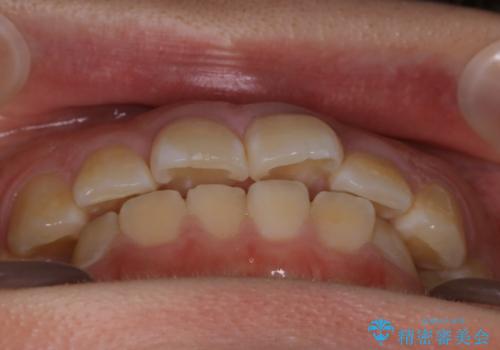

【非抜歯】ガタつきと歯軸を正して長持ちする歯へ

- 歯のガタつきと噛み合わせの改善を主訴に来院されました。

非抜歯で、少量の奥歯の移動と歯列の拡大・IPRを駆使して主訴を改善するための治療計画を立案しました。